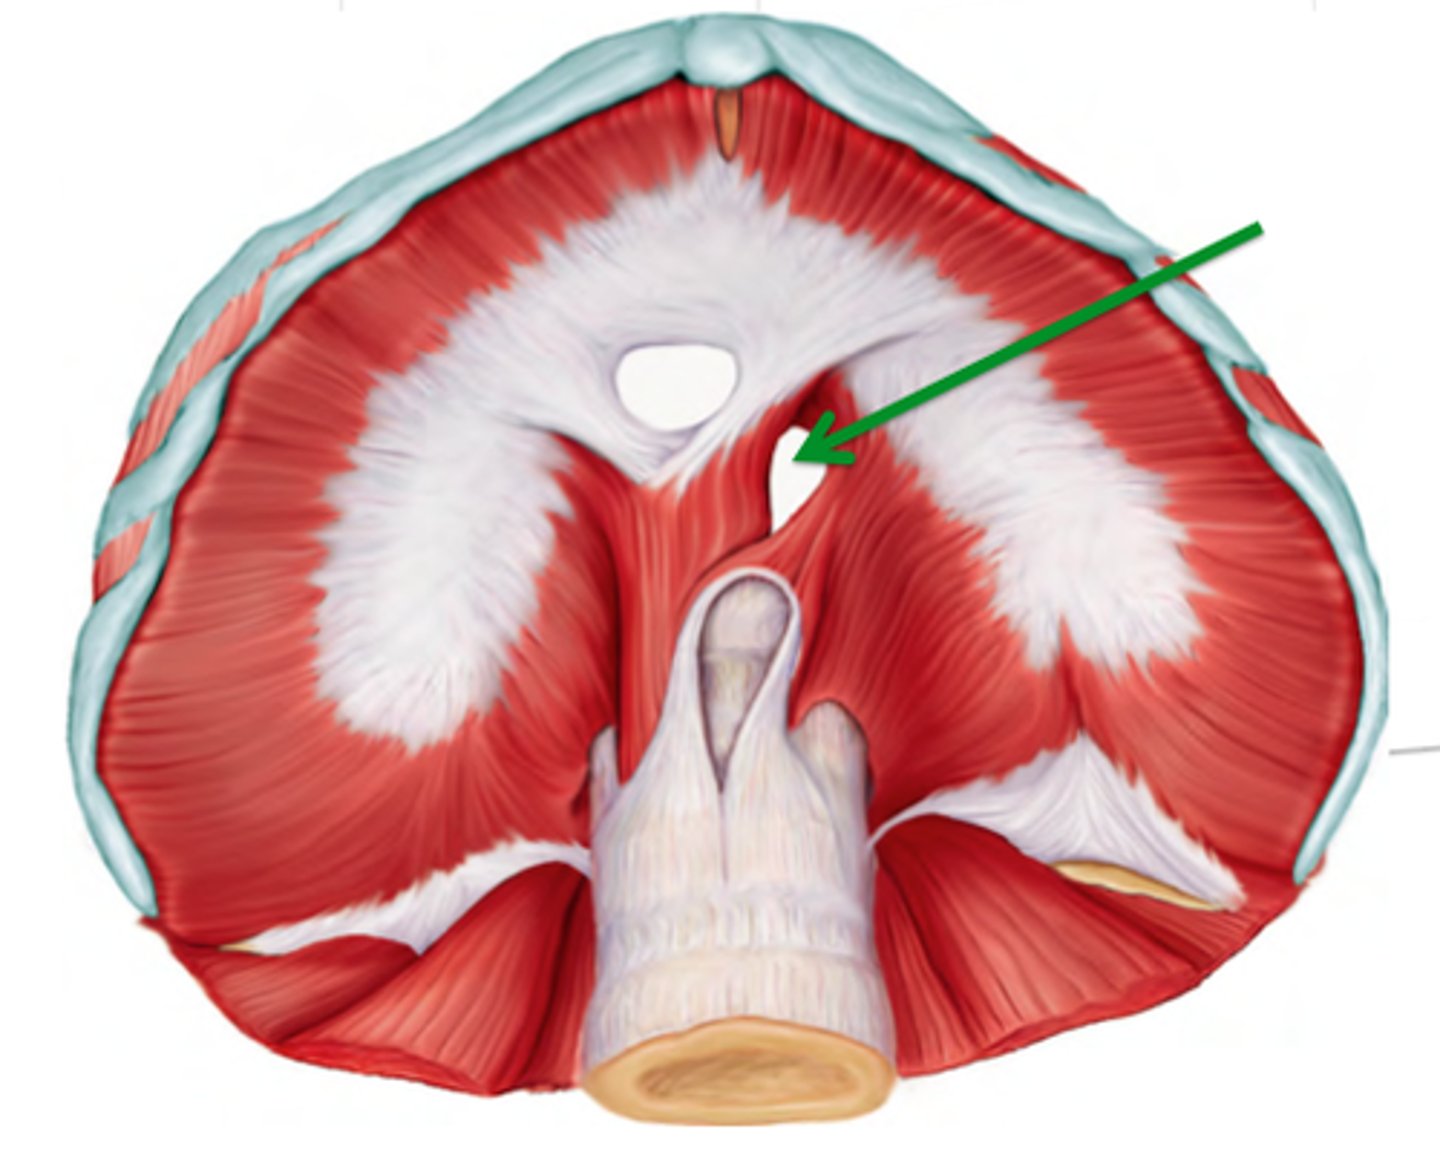

Oesophageal hiatus

allows the oesophagus to enter the abdomen to empty food into the stomach